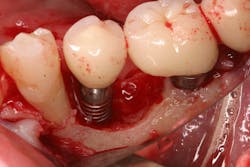

The literature is replete with case reports describing the infection and failure of a dental implant that is adjacent to a tooth with endodontic-induced apical pathology. Unfortunately, periapical lesions can travel to the dental implant and cause an exaggerated loss of attachment in a short period of time (figure 1).7 It is imperative that clinicians expeditiously diagnose and endodontically treat natural teeth with infections adjacent to dental implants.